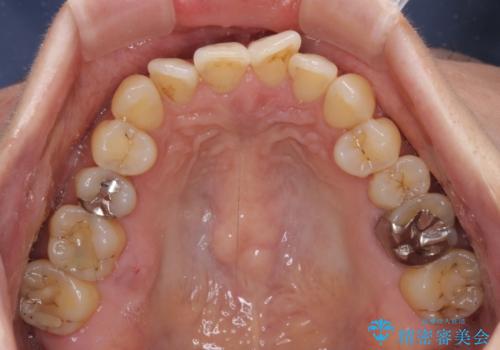

- 前歯のクロスバイトが気になり、インビザラインによる矯正治療を希望して来院された患者様です。

上顎側切歯(上の真ん中から2番目の歯)が舌側転位している場合、インビザラインでは仕上げきれないことが多く、更には無理して動かそうとすると歯髄壊死を起こすリスクが高いと言われています。

インビザラインで歯列を移動する前に、上顎前歯をワイヤー矯正で整え、その後上下歯列をインビザラインにて矯正治療を行うこととしました。